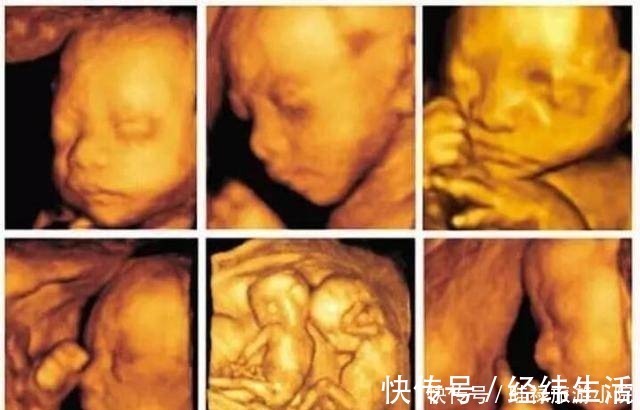

检查时间:怀孕中期,一般在孕24周时检查。现在不少医院大排畸检查,直接做四维B超,会看的更清楚些。排畸检查是孕期最系统的胎儿发育情况的检查,除了检查胎儿的外表可能存在的畸形外,也会检查胎儿内脏的发育情况等。【 产检|孕期产检不想生个“傻孩子”,这三项产检必须按时做,不能忽视】

京妈建议:① 四维排畸检查,一般需要提前预约,因此孕妈要提前咨询医生或护士,提前预约检查的时间;② 四维排畸检查因为看的比较仔细,所以检查时间较长,孕妈要有心理准备,不必担心:检查这么长时间是不是胎儿有问题;③ 孕妈提前做好准备,耐心的配合医生检查,别着急;④ 如果在检查过程中,胎宝宝胎动很少,孕妈可以起来走动走动,或喝点水、吃些甜食来刺激胎宝宝活动;⑤ 如果没能一次检查成功,比如胎儿正好挡住了某些部分,看不清楚,那就可以听从医生建议,安排时间再次检查,但不必慌张;⑥ 避免问医生些不该问的问题,比如关于胎儿性别,我国禁止非医学需要的胎儿性别鉴定,所以孕妈要配合医生,尽量避免问,如果问了医生不回答也是正常的,不要因此对医生生气或作出出格行为。⑦ 在胎儿大排畸检查时,一般会做胎儿超声心动检查,主要是了解胎儿各个心脏瓣膜以及心室、心房的发育情况,排除先天性心脏病的可能,孕妈听从医生的安排和建议就好。